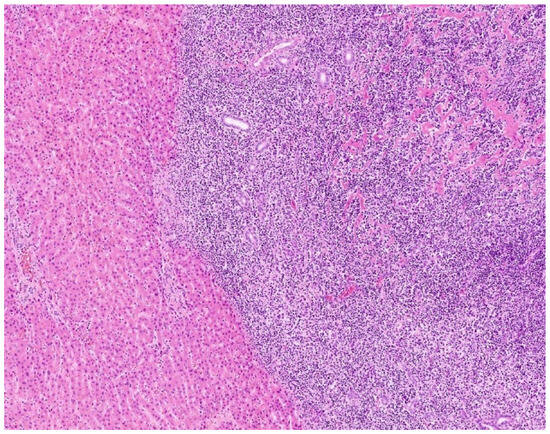

2.4. Pathology Findings